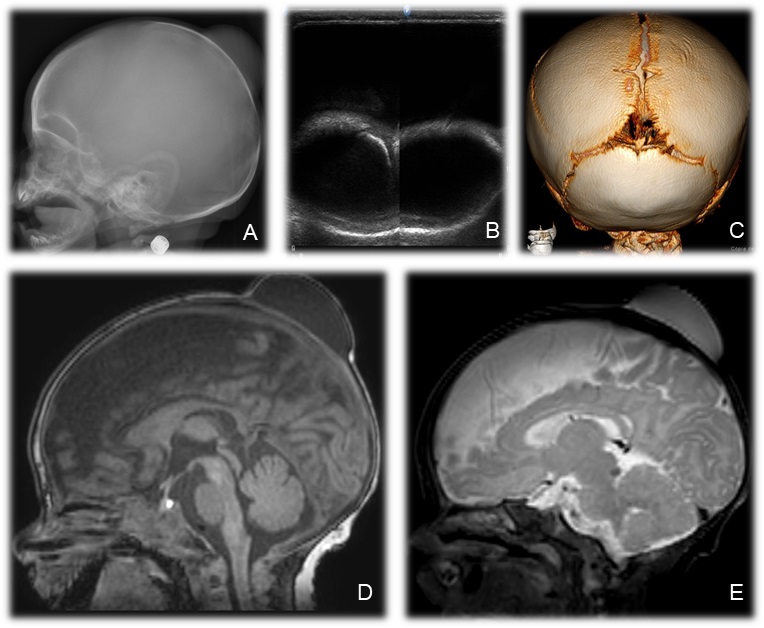

For initial evaluation, skull X-ray and cerebral ultrasound were performed (Figure 1). A magnetic resonance imaging and tomography of the brain were also performed (Figure 1).

A 30-day-old infant was brought to the pediatric emergency room with a bulge in the scalp in the parieto-occipital region, mobile and without associated phlogistic signs. He had no history of fever or any other complaints. The mother reported that the bulge appeared at 20 days of life and showed progressive growth. There was no history of trauma. The boy was born at term by cesarean delivery due to cephalopelvic disproportion.